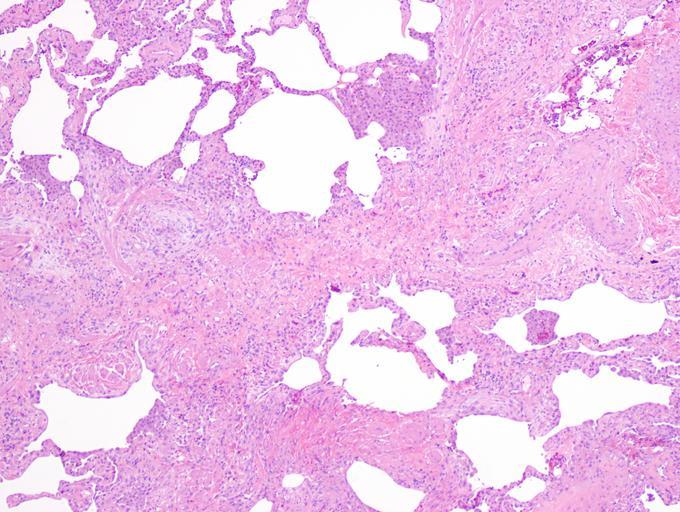

MAKE A MEME View Large Image UIPlungbiopsy.jpg en Appearance of usual interstitial pneumonia UIP in a surgical lung biopsy at low magnification The tissue is stained with hematoxylin purple dye and eosin pink dye to make it visible The pink areas in this picture ...

Keywords: UIPlungbiopsy.jpg en Appearance of usual interstitial pneumonia UIP in a surgical lung biopsy at low magnification The tissue is stained with hematoxylin purple dye and eosin pink dye to make it visible The pink areas in this picture represent lung fibrosis Note the patchwork quilt-like pattern of the fibrosis own Mutleysmith 2009-11-29 Histopathology of the usual interstitial pneumonia Biopsy